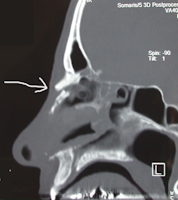

Aspects scannographiques de factures du nez